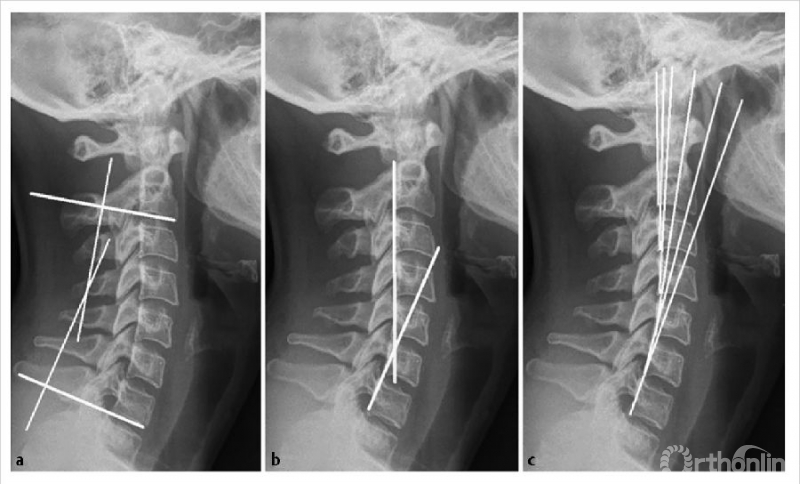

所有的测量都可以用颈椎的X光或CT扫描的矢状面来获得。mCM(图7a)的计算方法是先沿着C2和C7的椎体下终板画线,然后画垂直于两者的垂直线,垂直线相交处形成的角度即为颈椎前凸角。JPS(图7b)是沿着C2和C7的椎体后缘绘制的两条线的交点10,11。HPT(图7c)通过绘制平行于C2到C7椎体后缘的垂直线来计算,加上所有节段的角度。

图7 矢状位X线片显示用于测定颈椎前凸的改良Cobb法(a)Jackson生理应力线(b)Harrison后切线(c)(经Scheer等允许使用2)